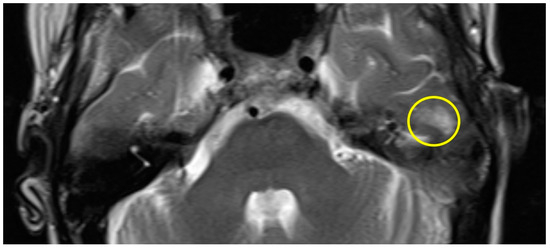

| slight (1) | parts of the inferior temporal gyrus, less than half of the thickness (cranial-caudal) |

| Patient #1 | T2 | f | 58 | left | 12 months | 175 min | slight |

| Patient #2 | T2 | f | 62 | right | 16 months | 159 min | slight |

| Patient #3 | T2 | f | 57 | left | 11 months | 131 min | slight |

| Patient #4 | T1 | f | 49 | left | 12 months | 159 min | slight |